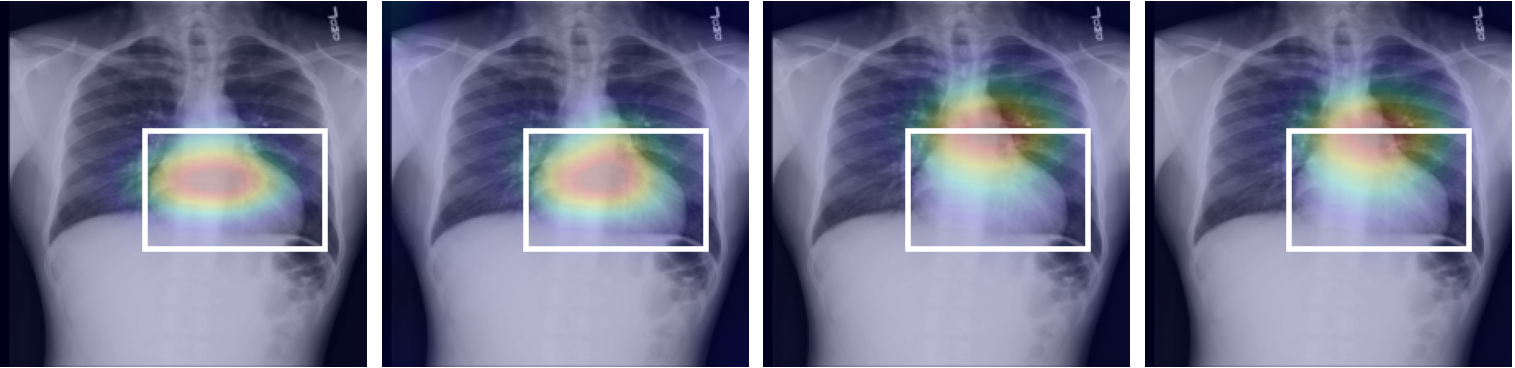

Linear Probing Evaluation: Table 1 presents the experimental results on NIH and SIIM-ACR datasets under linear probing protocol. Specifically, the parameters of encoder remain frozen while that of the linear layer get updated. For NIH, we evaluate the performance by sample labeled subsets from the official train set and report the official test set results in terms of AUC score. Similarly, on MuRed and ODIR datasets, the test set AUC score is reported by evaluating 10% of labeled training data. For pneumothorax segmentation on SIIM-ACR, we report the results in terms of dice score by updating the parameters of the decoder network while that of the encoder remains frozen. Supervised learning (Sup.) notably yields lower AUC scores than the SSL methods. The proposed approach consistently outperforms other baselines across varying degrees of labeled data, specifically for the 1% subset from NIH, the our approach achieves the highest AUC score of 65.1% with an average performance gain of more than 3% from all the baseline methods. Fig 2 presents the diagnostic maps for different pathological conditions, corresponding to the 10% labeled samples from NIH. A similar trend is observed for MuReD and the ODIR dataset, where the proposed approach outperforms the baselines with a considerable average margin of more than 3%. This indicates the method’s ability to extract meaningful representations from unlabeled data for the subsequent downstream training using limited labeled samples. Furthermore, a similar improvement in AUC scores is observed with increased labeled data. The proposed approach also results in the highest dice score of 57.5% on pneumothorax segmentation, with an improvement of 1% compared to the best-performing baseline.